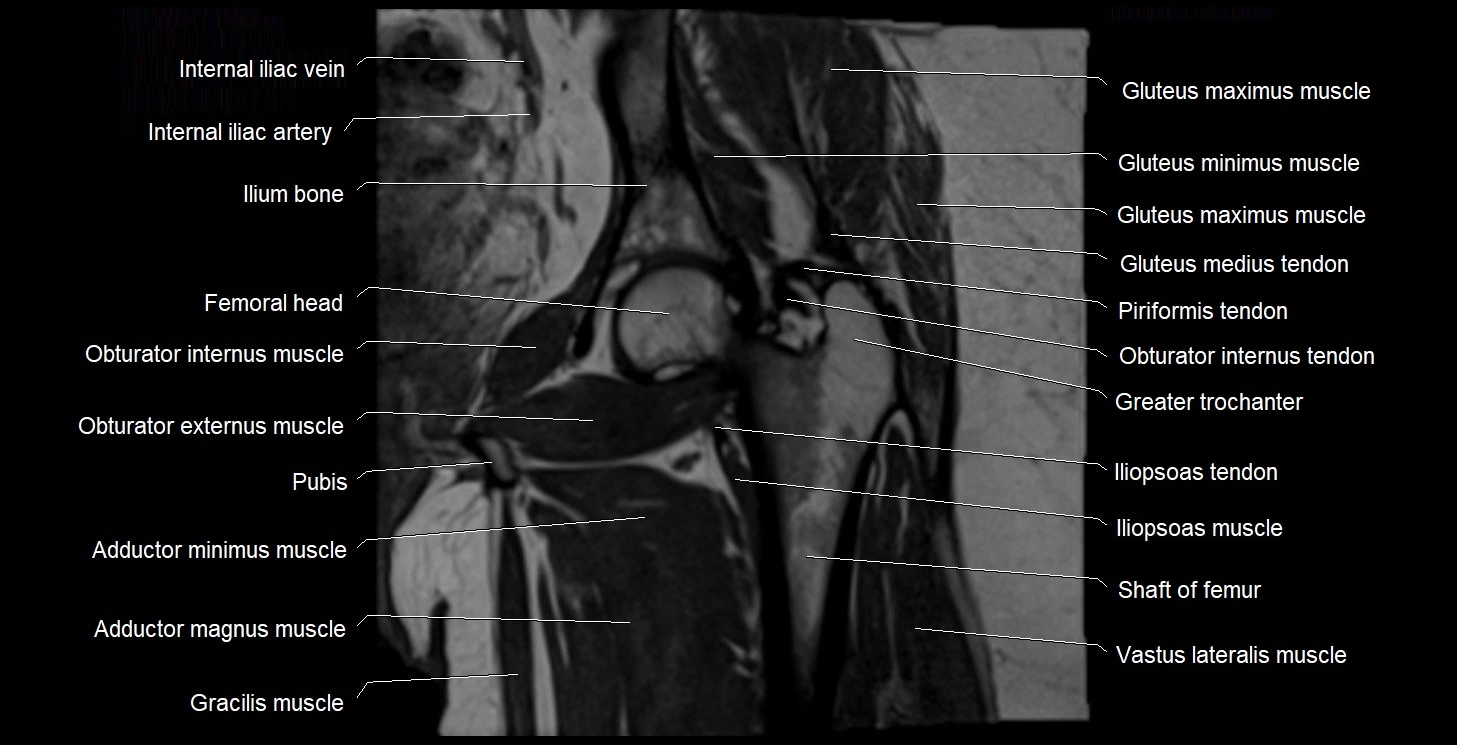

- Gluteus maximus muscle

- Gluteus medius muscle

- Gluteus medius tendon

- Gluteus minimus muscle

- Gluteus minimus tendon

- Gracilis muscle

- Greater trochanter

- Head of femur

- Iliopsoas muscle

- Iliopsoas tendon

- Ilium bone

- Obturator externus muscle

- Obturator internus muscle

- Obturator internus tendon

- Vastus lateralis muscle